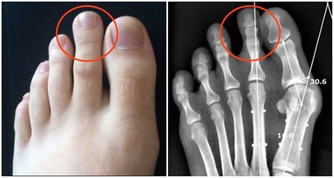

翻拍微信下同 其次當他入睡後依然維持了一個錯誤姿勢:側睡加頭低,導致頸部肌肉收緊,刺激了交感神經興奮,導致冠狀動脈平滑肌痙攣,心肌缺血,心梗而死。 頸椎病引起心臟病?是的! 專家說有可能!有一種心臟病就叫做頸源性心臟病,主要症狀包括如心前區作痛,心律失常,還會有胸悶不適感、心悸、氣促等。 看了下面數字,你怕不怕! 100個人中就有70個以上的頸椎病患者。 100個中風病症患者中有90%以上是由頸椎病引發的併發症。 100個腦癱病症患者中有63%以上是由頸椎病引發的併發症。 100個高位截癱病症者中有85%以上是由頸椎病引發的併發症。 100個猝倒死亡病症者中有95%以上是由頸椎病引發的併發症。 100個心肌梗塞病症者中有70%以上是由頸椎並引發的併發症。 100個腦血栓病症者中有80%以上是由頸椎並引發的併發症。 100個高血壓病症者中有60%以上是由頸椎並引發的併發症。 100個神經性胃潰瘍病症者中有75%以上是由頸椎並引發的併發症。 頸椎病有多要命?很危險! 更可怕的是,醫學上還發現頸椎病至少可引發全身70種病症,以下是幾種常見的病症。 1 吞咽不暢:吞咽時有梗阻感、食管內有異物感,少數人有噁心、嘔吐、聲音嘶啞、乾咳、胸悶等症狀。 2 視力障礙:視力下降、眼脹痛、怕光、流淚等,甚至還可能失明。 3 腹脹便秘:部分頸椎病患者因鄰近的頸交感神經受到刺激和損傷,使受其支配的內臟器官胃腸道蠕動減慢。 4 高血壓:血壓明顯升高,稱為「頸性高血壓」。由於頸椎病和高血壓皆為老年人的常見病,故二者常常並存。 5 胸痛:單側胸大肌和乳房疼痛,檢查時有胸大肌壓痛,這與頸六和頸七神經根受頸椎骨刺壓迫有關。 6 猝倒:站立或者走路時因突然扭頭出現身體失去支持力而猝倒,倒地後能很快清醒。 7 下肢癱瘓:早期表現為下肢麻木、疼痛、跛行,個別患者還有排便、排尿障礙,如尿頻、尿急或大小便失禁等。 8 老年痴呆:一旦頸椎間盤突出導致橫突孔變細、變形,會致使所供應的腦區發生供血不足,慢性腦缺血引起了遺忘等認知功能下降,長期以往最終會出現痴呆。 這頸椎病看著不起眼,可對我們的生命健康的威脅可是非常大! 奉勸頸椎不好的朋友千萬要當心,不要耽誤自己。在這裡提醒你,也希望你看到後提醒身邊的人:一定要關注自身的頸椎健康,別哪天被這頸椎病要了性命還不知道! 而很多人認為頸椎病不是很要緊的病,休息休息就好了,但是拖延下去,治療會越來越難,有的甚至要做手術治療,更嚴重的估計就會重演李建華的悲劇。所以勸大家及早預防,儘早治療! 脖子為什麼一轉就響? 因為我們身體的氣血供應不上,導致我們身體在變硬,關節在處於缺血狀態下的干磨。 氣血雙虧的身體相當於車軸里沒了油,很多人騎過自行車,知道如果車軸里缺油了,會感覺怎樣?一定是騎著費勁,一定會感覺裡面的滾珠轉動不靈活且有響動,有點類似我們的脖子響。只不過,自行車軸轉動靠的是油,而我們骨頭之間的轉動靠的是血液罷了。當我們血氣雙虧的時候,我們的骨關節之間的椎間盤,沒有充足的氣血供應,會形成干磨的情況,響動也就自然產生了。 骨關節為什麼會有病變? 1生理結構 人的頸椎和腰椎特別容易出問題,但胸椎卻好得多。這是因為我們的胸椎周圍有肋骨牽拉保護著,形成了一種力的相互作用,以確保我們的胸椎能夠保持中正。但是,頸椎和腰椎就不同了,它們沒有肋骨牽拉固定著,它們靠的是多組韌帶和小肌肉群。如果這些組織發生問題,就會導致我們的頸腰椎出問題。 2工作姿勢 當肌肉長期處於緊張狀態,就會感覺肌肉酸痛。正常情況下,如果胳膊腿酸了,我們活動一下,這樣的現象會很快消失,但是,用電腦就不一樣了,由於我們是長時間處於微弱的緊張狀態,這就好比溫水煮青蛙一樣,等我們查覺的時候,就已經晚了。它造成的後果就是,頸腰椎周圍的韌帶由於得不到充足的氣血供應,就會慢慢形成鈣化,兩側的牽拉受力開始不均勻,久而久之,椎間盤就會突出,擠壓周圍的組織和神經,頸腰椎病就會形成。 3工作環境 如果再加上工作環境的寒和濕比較嚴重,比如,在地下室工作、在空調底過的情況下工作,都會造成環境中的寒和濕進入到體內,特別是對於那些氣血本來就不夠通暢的肌肉和韌帶,會形成潛在的影響,加重了病變部位的病情。 4過食碳酸飲料 碳酸飲料會導致內脫鈣,久而久之,我們的骨頭變會得非常的疏鬆,那個時候,就不單純是骨頭響的問題了,而且還很容易導致骨折。 我們該如何調理? 下面介紹簡單易學的保護頸椎,甚至可以治好頸椎病的方法,大家一定要記好了! 1多多活動 天天以電腦為伴的朋友,用一會兒電腦,就要起來活動一下,同時活動一下脖子,但千萬不要做360度的圓周運動,只作90度向左轉,向90度的向右轉的動作,以確保我們脖子兩側的韌帶在短時間內,都能夠得到均衡的牽拉,以改善局部供血。而且切記動作要緩慢。 2不要讓頸部受涼 其是不要讓頸椎吹到冷風。頸椎受涼之後寒濕之氣很容易進入體內,而加重頸部韌帶的鈣化。 3杜絕碳酸飲料 減少包括可樂在內的一切碳酸飲料的攝入,因為這種溫水煮青蛙的過程是漸進的,因此很難被人們重視。 4打通經絡 這點最為重要。如果是脖子不舒服,最簡單的方法就是以自己的下巴寫米字,一天做一次即可,或在桌子邊擱後溪穴,以確保頸椎部的血液循環,使自己的頸椎摸著是溫暖的,而不是冰涼的。 5滾一滾、滾出好脊椎 站立歪斜或坐姿不端正、習慣性翹腳、長時間玩手機或者是坐在電腦前都會造成我們脊椎歪曲不直,脊椎一旦彎曲歪斜,很多毛病會跟著來。 中老年朋友可以常常做滾背的動作,矯正脊椎,甚至有人長了骨刺也可以治癒哦!每天勤快108下(來回一次算一下),骨刺免開刀,不用快慢慢做,矯正脊椎自己來! 滾背方式: 1、並腿屈膝坐在地上,兩手環抱住小腿,自然呼吸別太急促,收腹拱背,身體往後從尾椎、腰椎一節一節觸及地面,剛開始腳還先不用越過頭,多做幾下後再視自己身體狀況,然後滾到胸椎、頸椎,腳尖朝上,漸漸地雙腳越過頭,腳打直腳尖著地。